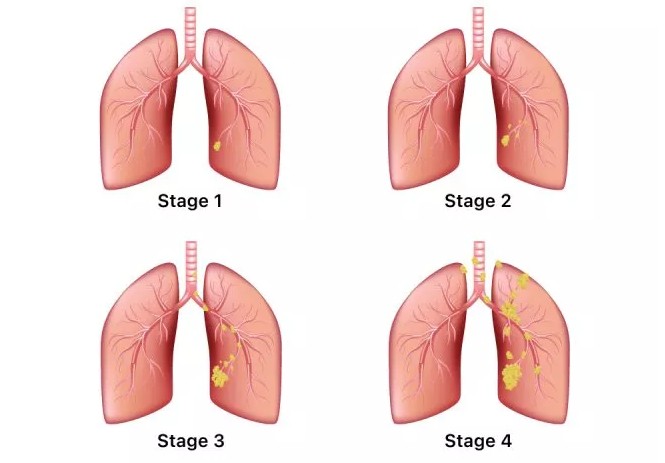

폐암은 암세포가 커지거나 주변 기관으로 전이되면서 다양한 증상을 유발합니다. 증상이 나타났을 때는 이미 어느 정도 진행된 경우가 많으므로, 아래 증상들을 주의 깊게 살펴봐야 합니다. 다음은 폐암 환자들이 흔히 겪는 10가지 주요 초기 증상입니다.